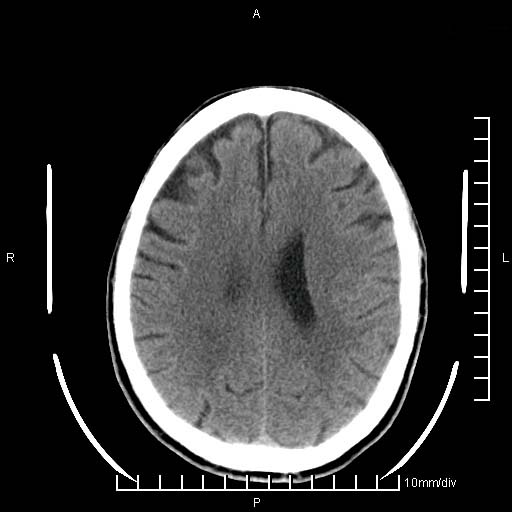

临床以双下肢浮肿,疼痛收治,无明显神经系统症状,既往无梗塞,出血病史。左颞叶见低密度灶,考虑什么?

考虑左侧颞叶脑软化灶。

无强化 无占位 软化灶吧

无强化、 无占位、局部脑沟增宽, 软化灶吧。